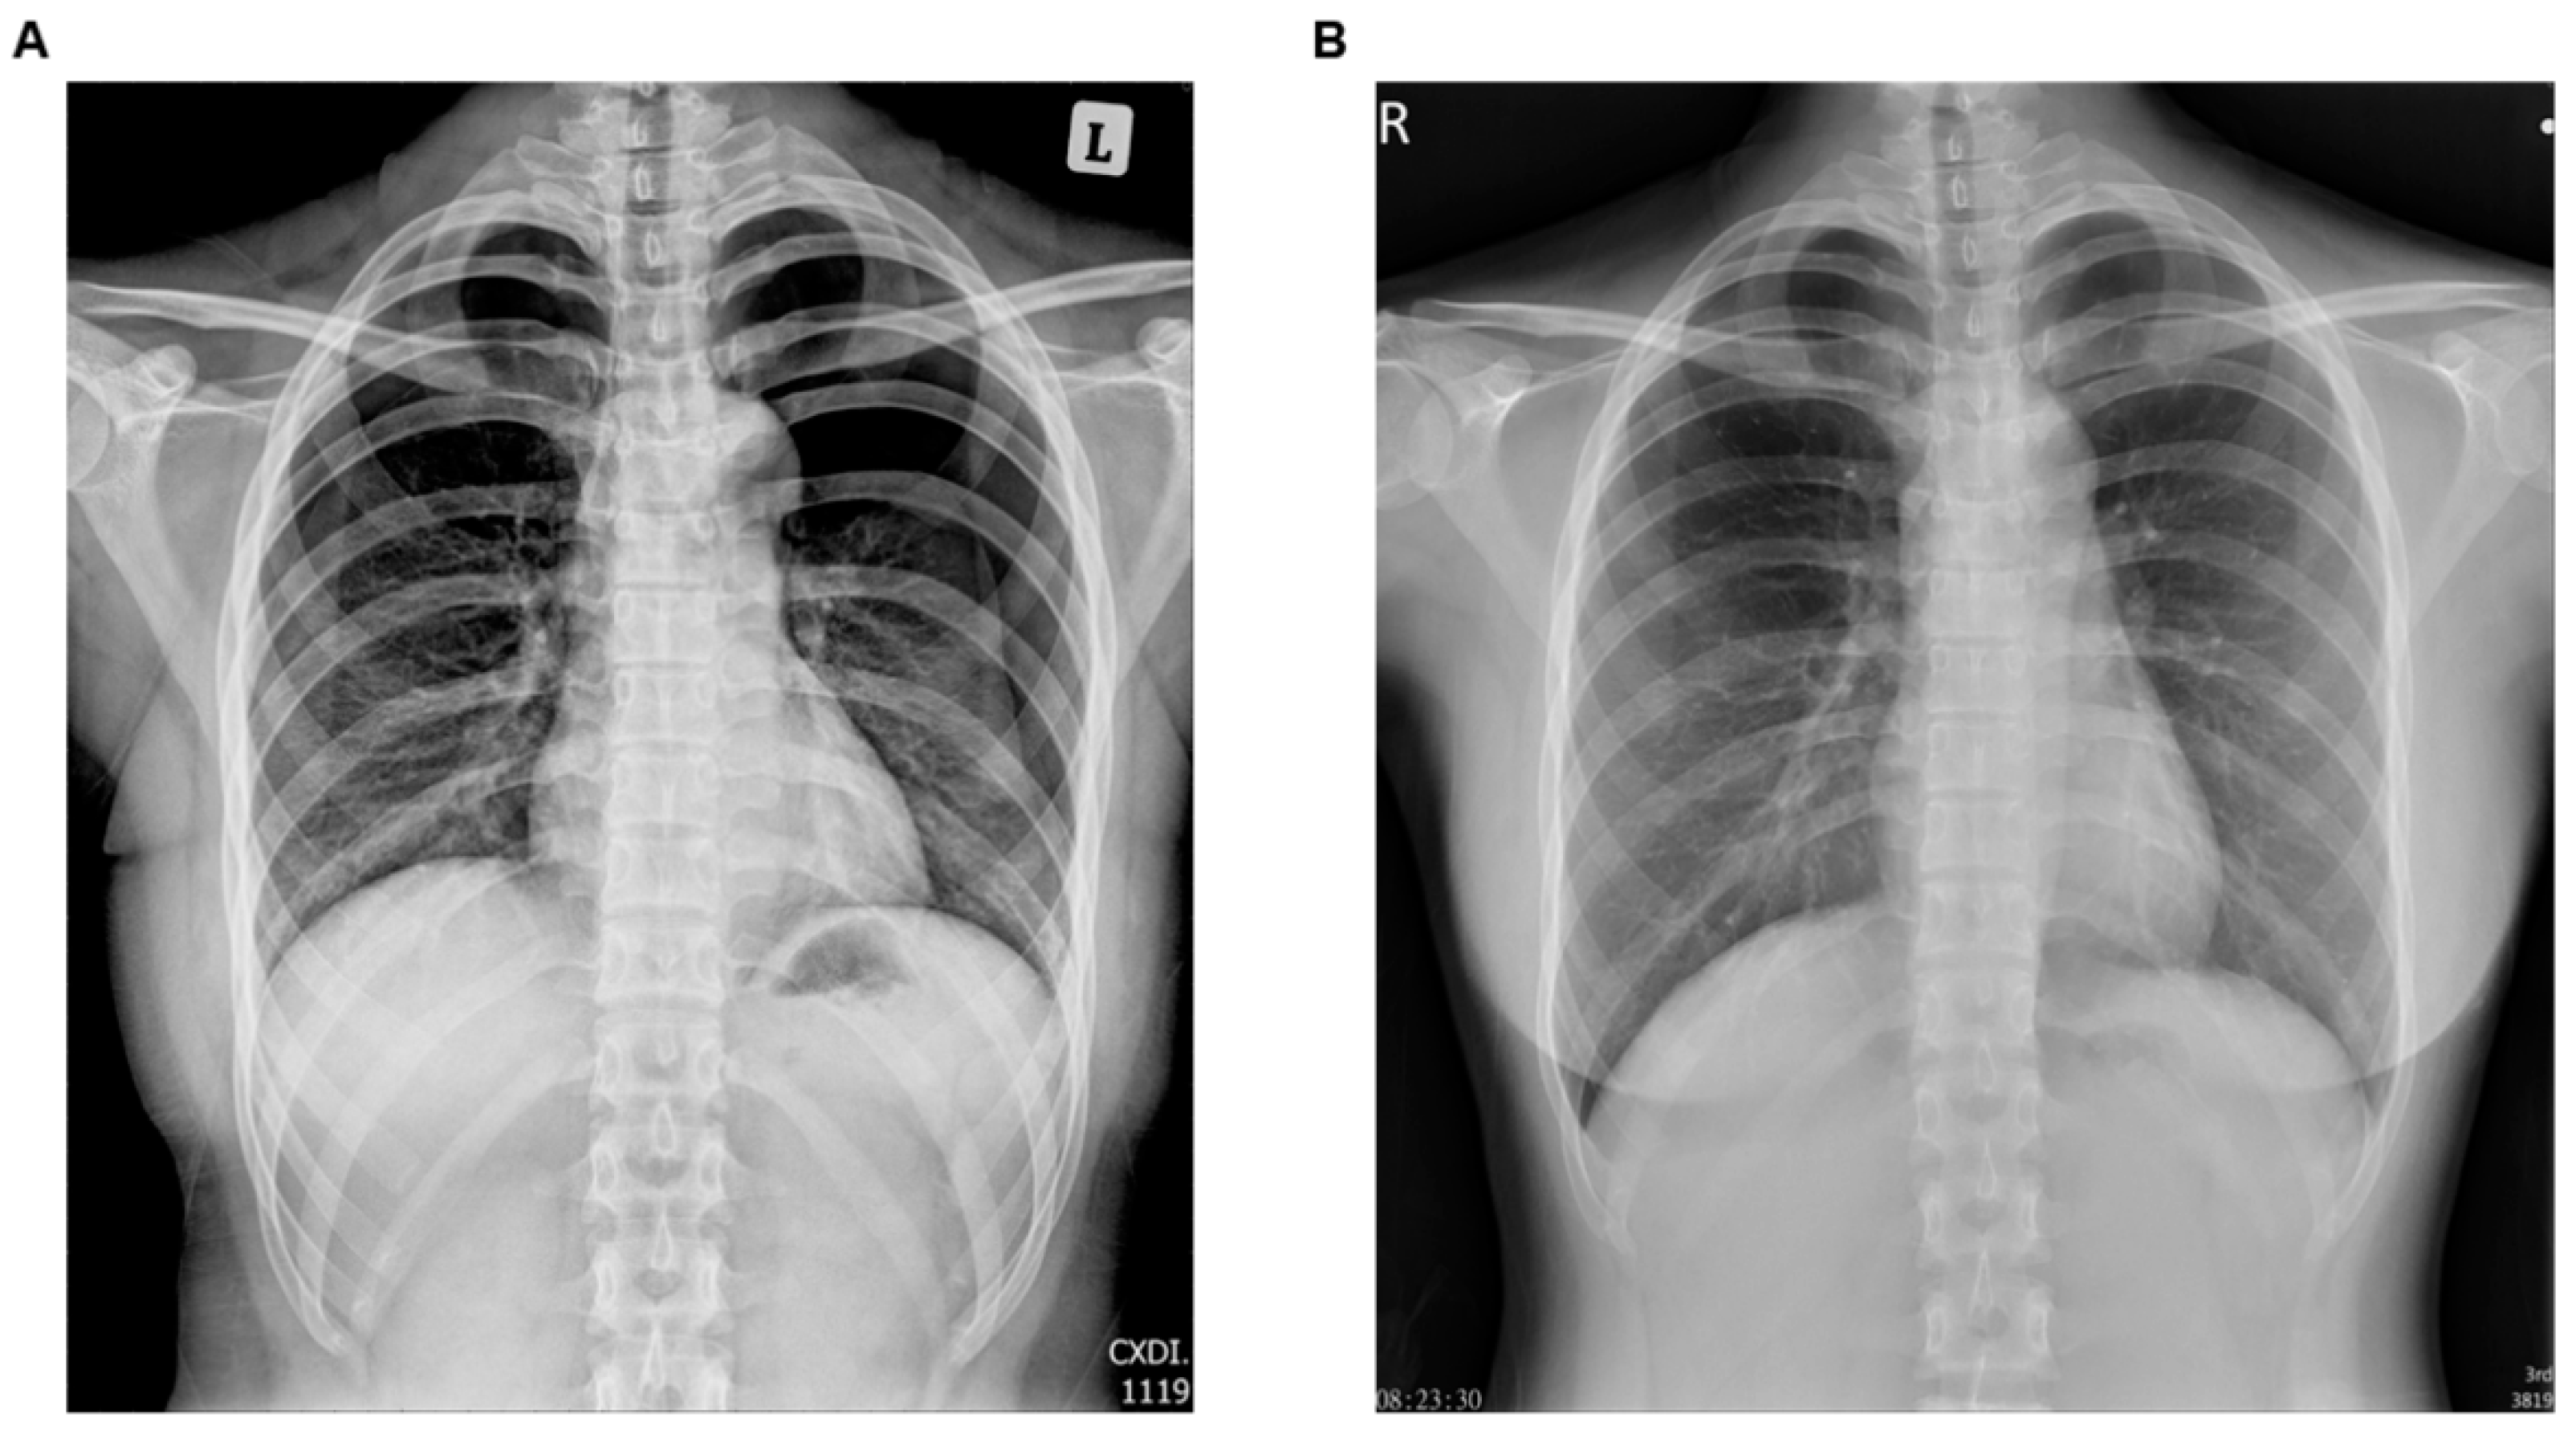

Medicina Free FullText Iatrogenic Pneumothorax during Acupuncture

From www.mdpi.com

Medicina Free FullText Iatrogenic Pneumothorax during Acupuncture Acupuncture Needles Xray Traditional chinese acupuncture involves placing needles into the subcutaneous tissues along predefined meridians, and later totally removing. These were determined to be permanently implanted acupuncture needles. In some practices, the needle remnants are left permanently in the tissue to provide continuous neurological stimulation, also known as hari. We describe the imaging appearance of these. Needle movements such as lifting, inserting,. Acupuncture Needles Xray.